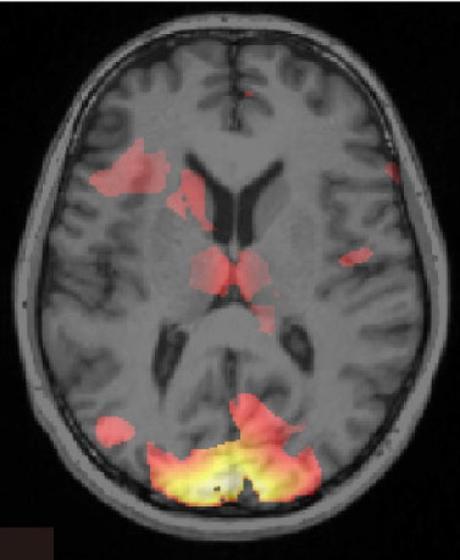

Escaneo del cerebro donde se visualiza información asociada con una memoria de miedo específico.